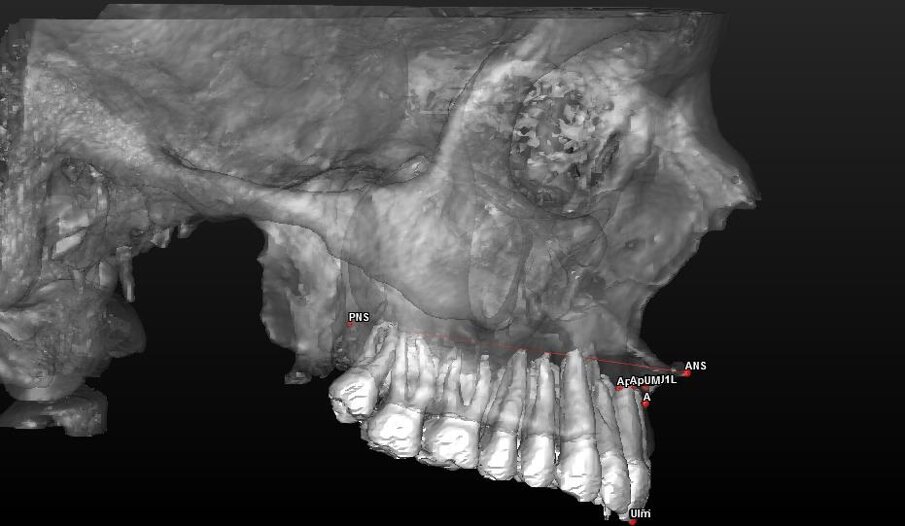

- 7 landmark per la valutazione scheletrica (Tab. 1) (Figg. 2, 3).

UIm: Punto mediano dei margini degli incisivi U11 e U21;Dai landmark dentali (U11, U21, ApU1R e ApU1L) sono stati ricavati due punti mediani calcolati direttamente dal software:

- ApUM: Punto mediano degli apici degli incisivi ApU1R e ApU1L.

Con questi è stato possibile tracciare una retta che passasse tra i punti UIm e ApUM e che possa essere considerato così il vero asse mediano degli incisivi centrali definendolo “Asse Incisale Superiore”.

Dai landmark ossei ANS e PNS è stata tracciata una retta passante per questi due punti definita “Asse Spinale”.

Componente dentale (Tab. 4) (Figg. 8, 9):

Fig. 8_Valutazione della componente dentale in visione para-frontale.

Fig. 9_Valutazione della componente dentale in visione di profilo.